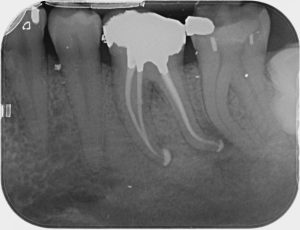

Root Canal / Retreatment

Clinical Cases